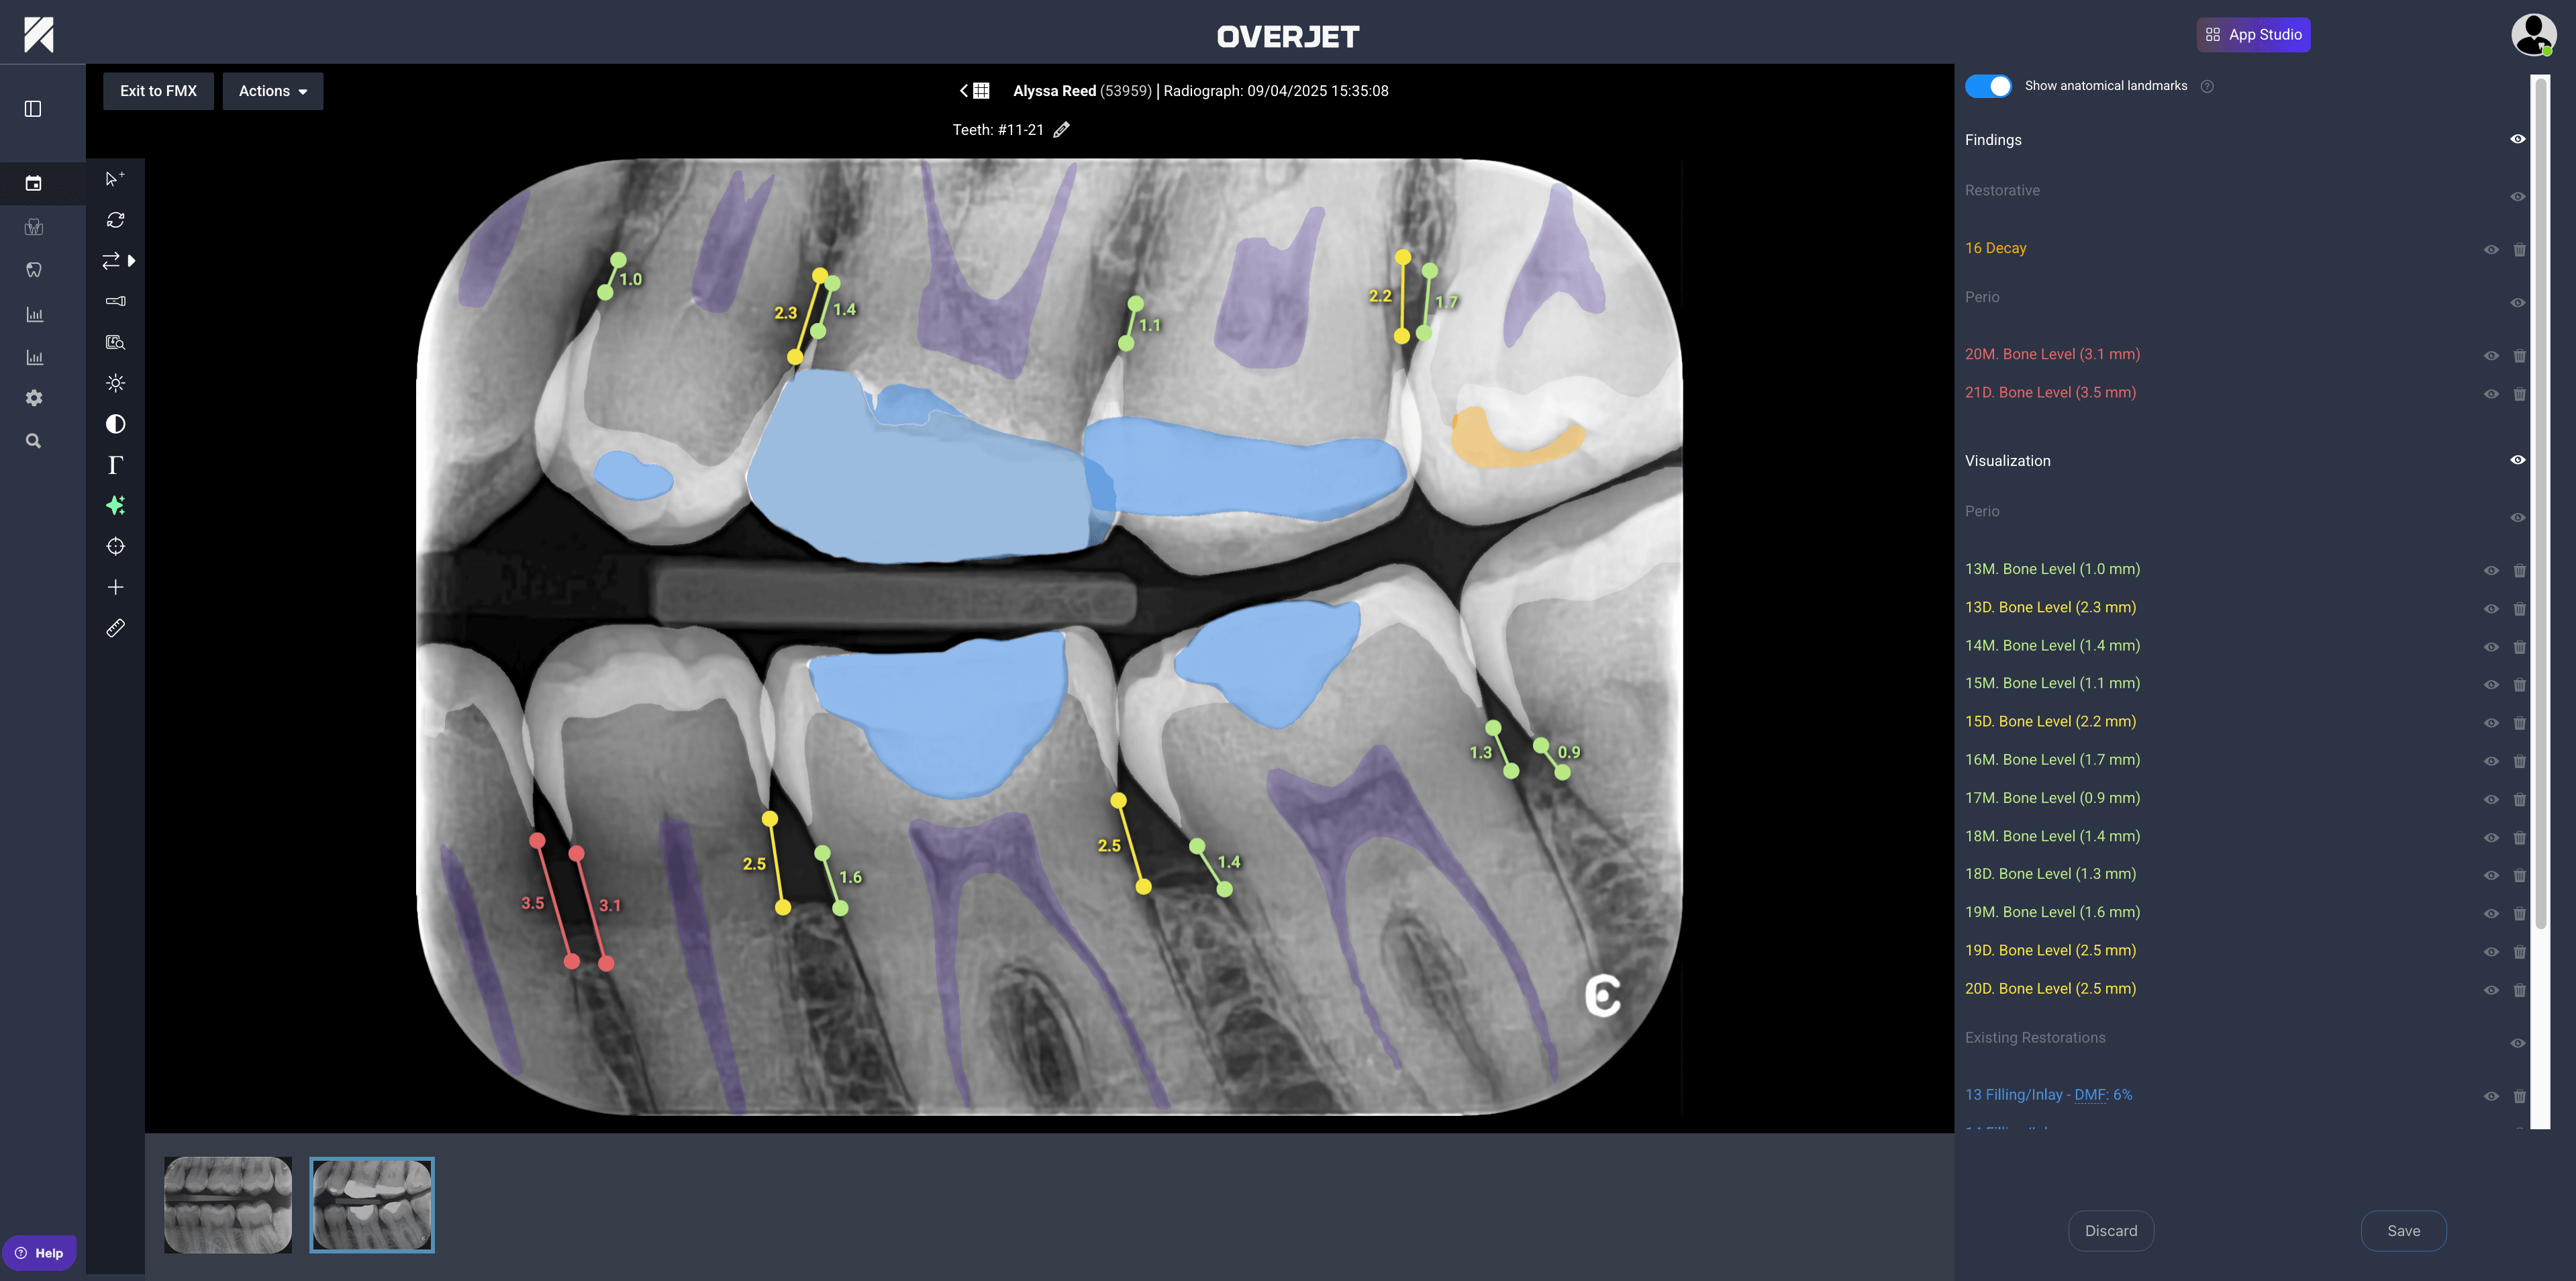

Step 3: Visualize findings for clinical review

After analysis, AI-generated findings are displayed using clear, color-coded overlays that make complex radiographic information immediately accessible. Each tooth or site can be reviewed individually, with millimeter labels from the cementoenamel junction (CEJ) to the bone crest providing precise measurements. These visual aids transform abstract radiographic data into actionable clinical insights.

The ability to compare baseline and current images side by side proves particularly valuable for tracking disease progression or treatment outcomes over time. Toggle controls allow overlays to be shown or hidden during chairside conversations, giving clinicians flexibility in how they present findings to patients.

This adaptability makes it easier to explain conditions without overwhelming patients with technical details, while still providing the visual evidence needed to support treatment recommendations.

For instance, the system provides an annotated case with millimeter labels and a per-tooth chart, which makes it easy to communicate findings to patients and provide objective evidence for insurance claims.

How does Overjet measure periodontal bone levels in millimeters?

Overjet uses FDA-cleared algorithms to quantify the distance from the cementoenamel junction (CEJ) to the bone crest in millimeters, providing per-site measurements for objective periodontal assessment.